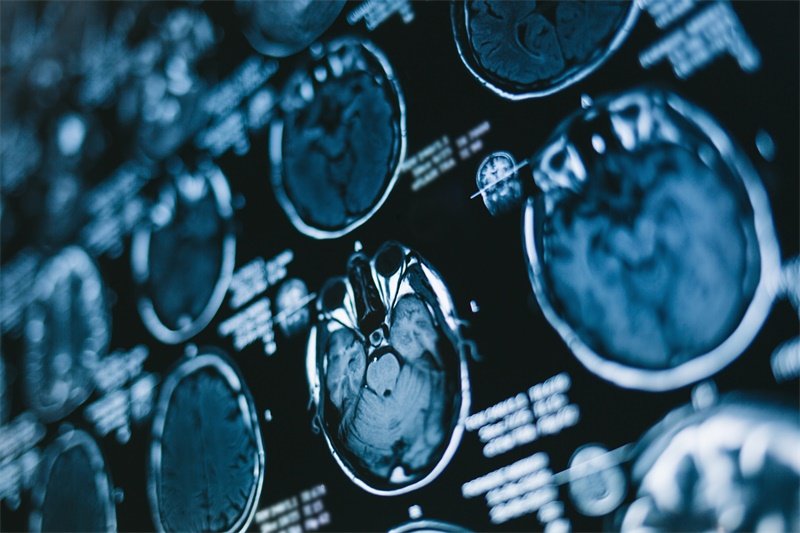

诊断大脑镰前部占位性病灶通常需要多种方法的结合。首先,医生会进行详细的病史询问和体格检查。接下来,一系列影像学检查是必不可少的,其中包括CT扫描和MRI扫描。

MRI扫描

MRI扫描提供更加细致的软组织影像,能够更清晰地显示镰前部的结构和占位性病灶。这对于明确诊断、评估肿瘤大小及其对周围组织的影响起着关键作用。